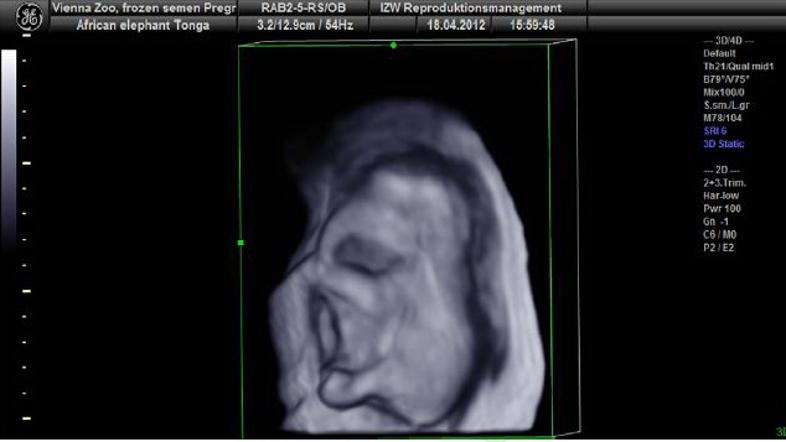

Slonica ZOO Schönbrunn / Daniel Zupanc

V dunajskem živalskem vrtu so uspešno oplodili slonico. Zarodek je trenutno star devet mesecev.

V dunajskem živalskem vrtu Schönbrunn je uspela oploditev afriške slonice Tonge s semenom samca, ki živi na prostem v Južni Afriki. Gre za prvo uspešno umetno oploditev slona z zamrznjeno spermo na svetu. Zarodek je trenutno star devet mesecev, vendar bo na skotitev mladička treba počakati še kar nekaj časa, saj so slonice običajno breje kar 22 mesecev, so sporočili iz Agencije za stike z mestom Dunaj.

Da so veterinarji lahko pridobili spermo samca, ki živi v južnoafriškem rezervatu Phinda Private Game Reserve, so ga morali najprej uspavati in mu z električnim spodbujanjem odvzeti seme. Novembra lani so na ta način uspešno oplodili 26-letno slonico Tongo iz dunajskega živalskega vrta. Devet mesecev star zarodek je zdaj velik približno 20 centimetrov, spola pa mu še ne morejo določiti.